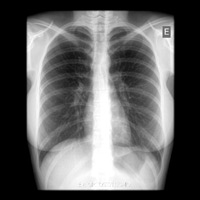

Exames

Raios X

O que é o exame?

O sistema de Raio-X Digital apresenta uma melhor qualidade e precisão da imagem gerada por raio-X principalmente mais saúde ao paciente devido a menor exposição a radiação ionizante.

Os problemas comuns na manipulação e processamento de películas convencionais são minimizados com o sistema de Raio-X Digital, reduzindo desta forma o tempo de realização dos exames e eventuais repetições na aquisição de imagens pois, o sistema digital permite ajustes na imagem captada contribuindo também para uma menor exposição do paciente ao raio-X. O sistema de Raio-X Digital permite ainda o arquivamento de exames possibilitando o estudo comparativo entre exames anteriores e actuais, auxiliando o Médico na definição e no acompanhamento de quadros clínicos.

Como é feito?

O paciente posiciona-se em frente ou sobre o aparelho de raio-x acompanhado da orientação de um técnico. É emitido raio-x na região a ser estudada e ao mesmo tempo os raio-x são captados em uma placa especial, que será processada digitalmente formando a imagem da área de estudo. Esta imagem poderá ser gravada em cd-rom ou impressa em película. No sistema digital a imagem gerada é armazenada em cd-rom, que através de software específico pode-se obter a visualização, mensuração, ampliação e manipulação desta imagem auxiliando o Médico a obter maior precisão em seu diagnóstico e mais comodidade ao paciente em seu transporte devido ao tamanho do cd-rom em relação ao filme convencional.

Recomendações ao paciente

RX SIMPLES: não há preparação (Rx seios perinasais, tórax, cavum, articulações e etc..), salvo em casos específicos em que o médico solicita no pedido médico a realização de preparação para a execução do exame.